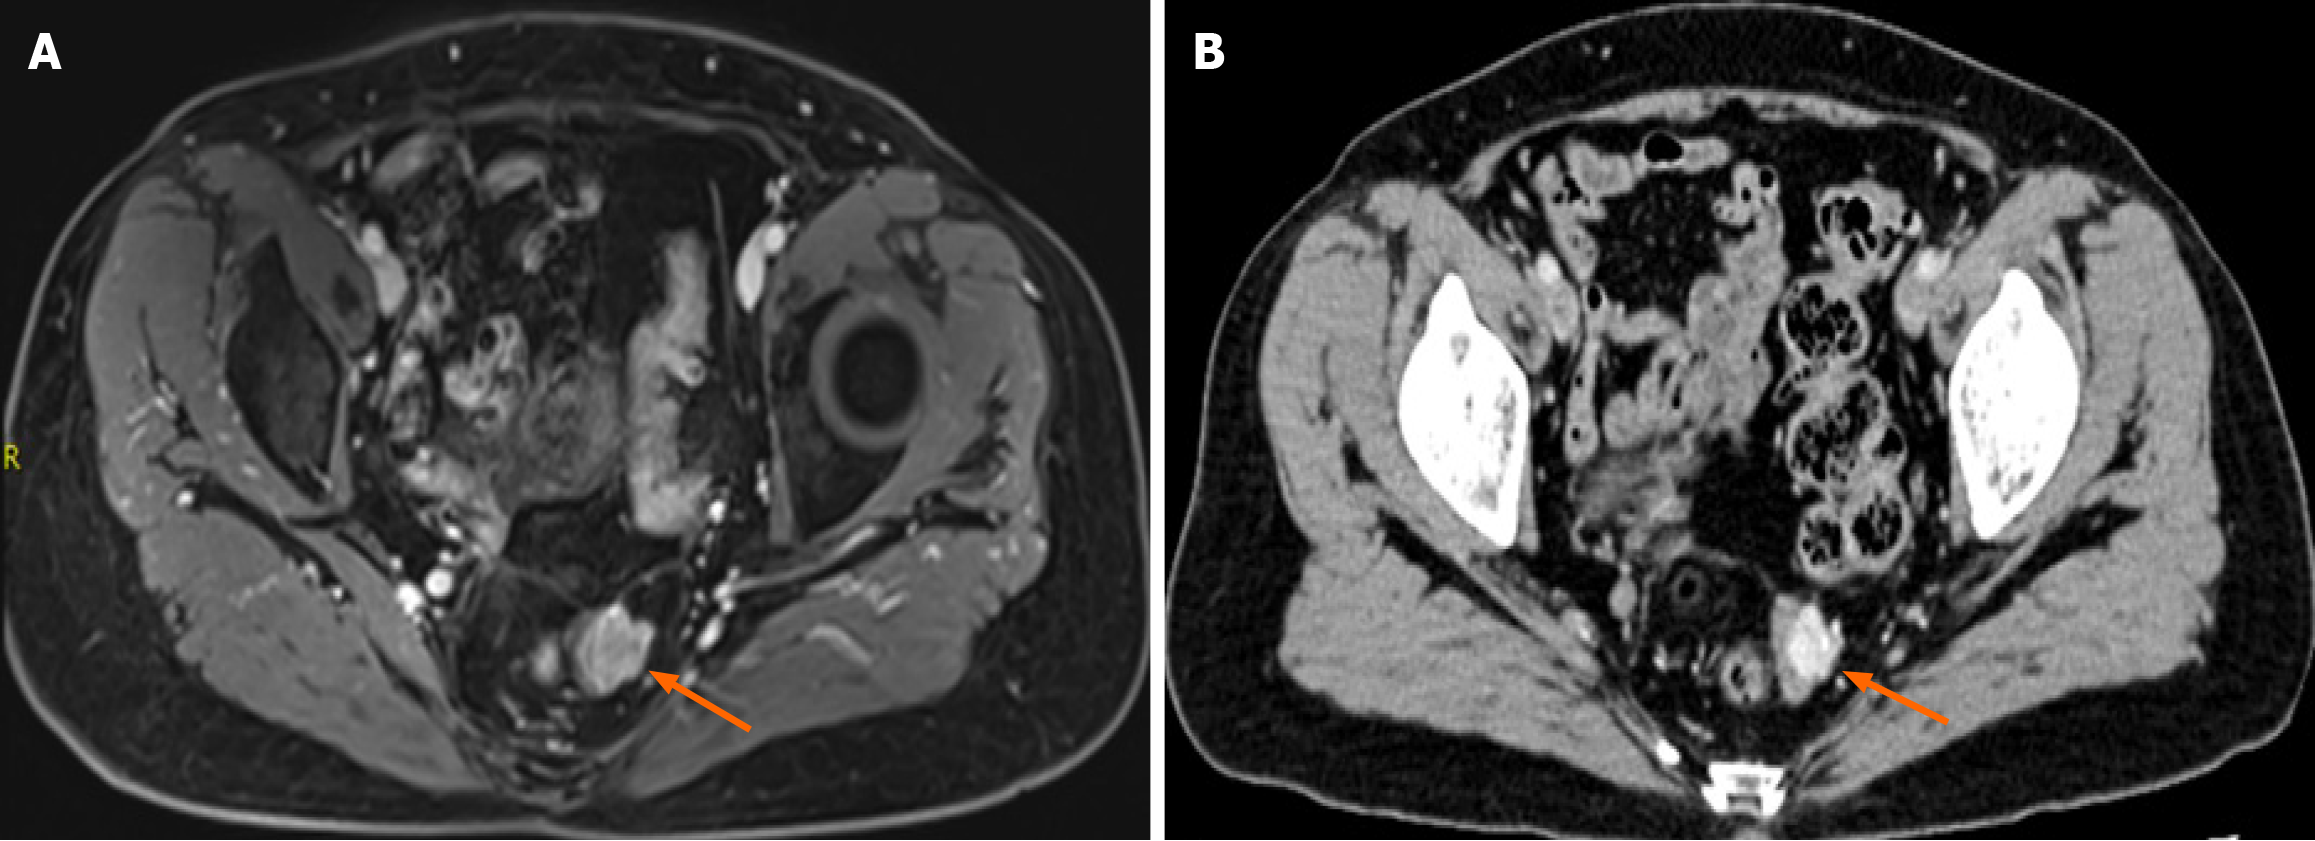

Pelvic magnetic resonance imaging (MRI) showed focal thickening of the upper rectal wall with a nodular mass protruding into the lumen (Figure 2A). Contrast-enhanced abdominal computed tomography (CT) confirmed localized rectal wall thickening with mild enhancement (Figure 2B).